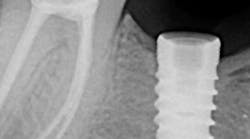

Artery forceps, explorers, spoon excavators, and Cavitrons have been used when the screw fracture occurs in the coronal third of the implant chamber (figure 1). The oscillations from an ultrasonic scaler can gradually reverse out the screw by placing the thin tip of an ultrasonic scaler directly on the top of the screw.8 Adding a lubricant, such as eugenol or mineral oil, can decrease friction and ease clamping to assist in screw retrieval.